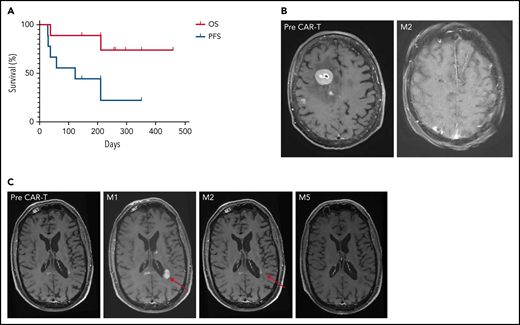

Between May 2020 and March 2021, 9 patients with R/R PCNSL were treated with anti-CD19 CAR T-cells: 7 received tisa-cel and 2 received axi-cel (Table 1). At time of infusion, the median age was 67 years old (range, 48-75 years) and median Eastern Cooperative Oncology Group (ECOG) scale of Performance Status was 1 (range, 0-4). Eight patients had brain parenchymal involvement, including 1 with intraocular localization, and 1 patient had an isolated cerebrospinal fluid (CSF) relapse. The median number of prior therapies before leukapheresis was 3 (range, 2-5), including ASCT in 7 patients. Bridging therapy was necessary in all but 1 patient because of the rapid evolution of R/R PCNSL and the time to manufacture CAR T-cells. At time of CAR T-cell infusion, following bridging treatment, 4 patients had progressive disease (PD) and 5 patients were in partial response (PR). One patient had ongoing corticosteroid treatment. The median follow-up after CAR T-cell infusion was 8.5 months. Seven patients experienced CRS (any grade), including 1 grade 3 after tisa-cel. ICANS of any grade occurred in 5 patients, including 1 grade 3 after tisa-cel and 1 grade 4 after axi-cel. Symptoms of ICANS included confusion, impaired handwriting, seizures, and status epilepticus. The median times from infusion to the onset of CRS and ICANS were 5 (range, 1-6) and 8 days (range, 5-21), respectively. The median times to resolution of CRS and ICANS were 3 (range, 2-9) and 4 days (range, 1-70), respectively. Four patients had grade 3 or higher cytopenia lasting more than 28 days. At 1 month (M1), OR was observed in 6 of 9 patients, including complete response (CR) in 3 of 9 patients. At M3, OR and CR were observed in 6 of 9 and 5 of 9 patients, respectively. Best response to CAR T-cells was PR in 1 of 9 (tisa-cel) and CR in 5 of 9 patients (2 axi-cel, 3 tisa-cel). Two patients died, 1 from PD and 1 from COVID-19 while still in CR. Median PFS was 122 days, increasing to 210 days for responders. Median DoR was not reached. Six-month OS, PFS, and DoR were 89%, 44%, and 67%, respectively (Figure 1A; supplemental Figure 1).

Survival and imaging of patients with R/R PCNSL treated with commercial anti-CD19 CAR T-cells. (A) OS and PFS. Median OS was not reached. Median PFS was 122 days for the whole cohort, increasing to 210 days for responders, vs 29 days for non-responders. (B) Patient 3: right frontal lesion at baseline and CR 2 months after CAR T-cell infusion. (C) Illustration of the flare effect suspected in patient 6: appearance of a left periventricular lesion 1 month after CAR T-cell infusion that dramatically decreased 2 and 5 months later. Despite high suspicion of a flare effect, response was reported as progressive disease according to the IPCG criteria, thus potentially underestimating PFS.

Patient 3 presented with high tumor burden and PD at time of CAR T-cell infusion, associated with an ocular infiltration. A remarkable response to CAR T-cells was observed, with a persistent CR on brain magnetic resonance imaging (MRI; Figure 1B). Because of a grade 4 ICANS with status epilepticus, an eye examination was not feasible. The level of interleukin-10 was measured at 1200 pg/mL in the anterior chamber at M6.16 A larger series is needed to evaluate CAR T-cell homing in the ocular compartment.

Patient 6 had an early brain MRI 9 days after CAR T-cell infusion because of clinical deterioration. New multiple contrast-enhanced nodular lesions of several millimeters were observed. On MRIs performed 7 and 19 days later, without any additional treatment, these lesions significantly decreased, but 2 new lesions appeared in the corpus callosum and left periventricular region (Figure 1C). These lesions then markedly decreased on subsequent MRIs at M2, M3, and M6. In parallel, clinical status dramatically improved, raising the potential of pseudoprogression linked to CAR T-cell therapy and the difficulty to assess the response.